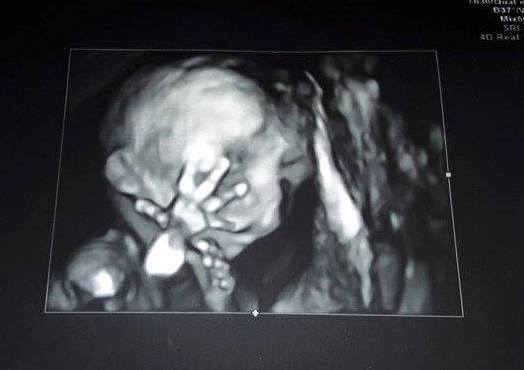

Ai împlinit 18 săptămâni și 2 zile. Ți-am văzut inima cum bate, astăzi te-am văzut mare și frumos. M-am panicat că

aveai cordonul ombilical în jurul gâtului și am întrebat medicul de 2 ori dacă

ești bine. Azi ți-am văzut mânuțele și piciorușele. Ți-am văzut mutrița aia

mică și am simțit o dragoste care nu se poate descrie în cuvinte. Am simțit

nevoia să-ți mângâi fruntea. Am început să plâng de nepuțintă și frustrare, de

dor de bunicul tău, iar tu atunci ți-ai dus mâna la față, puiule. Ți-ai dus

mână la față și apoi la ochi. Azi am conștientizat că toate suferința mea ai